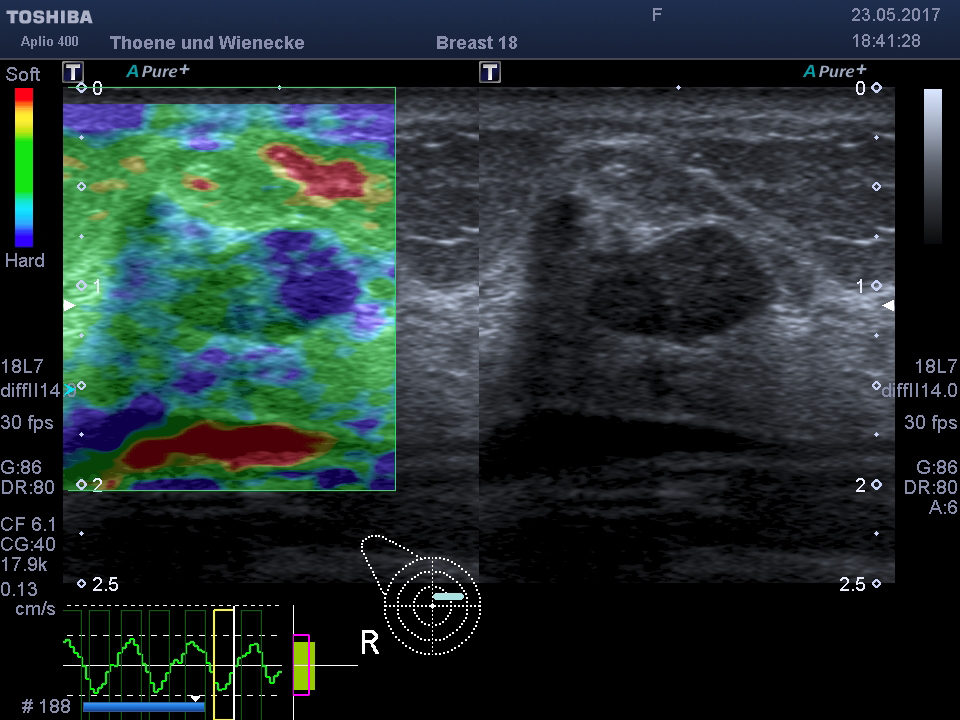

Der Ultraschall ist eine Untersuchung ohne Strahlenbelastung. In unsrer Praxis werden hochauflösende Ultraschallköpfe verwendet, die eine hohe Genauigkeit und sehr gute Auflösung ermöglichen. D.h. auch kleinste Veranderungen können schon gesehen werden. Mit der 3 D Sonographie können Veränderungen des Gewebes in ihrer Abgrenzung zum normalen umgebenden Gewebe besser beurteilt werden als nur mit der 2 D Methode. Bösartige Knoten bilden Ausläufer in das umgebende Gewebe, die wie kleine Strahlen einwachsen. Diese Phämomene können mit der 3 D Sonographie beurteilt werden, die Unterscheidung zwischen gutartigen und bösartigen Veränderungen wird genauer und die Rate an unnötigen Biopsien kann vermindert werden.